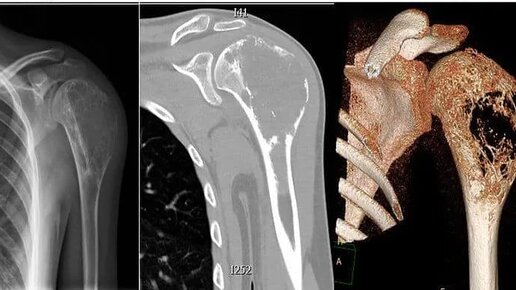

Злокачественные новообразования костей и суставных хрящей: остеосаркома, саркома Юинга